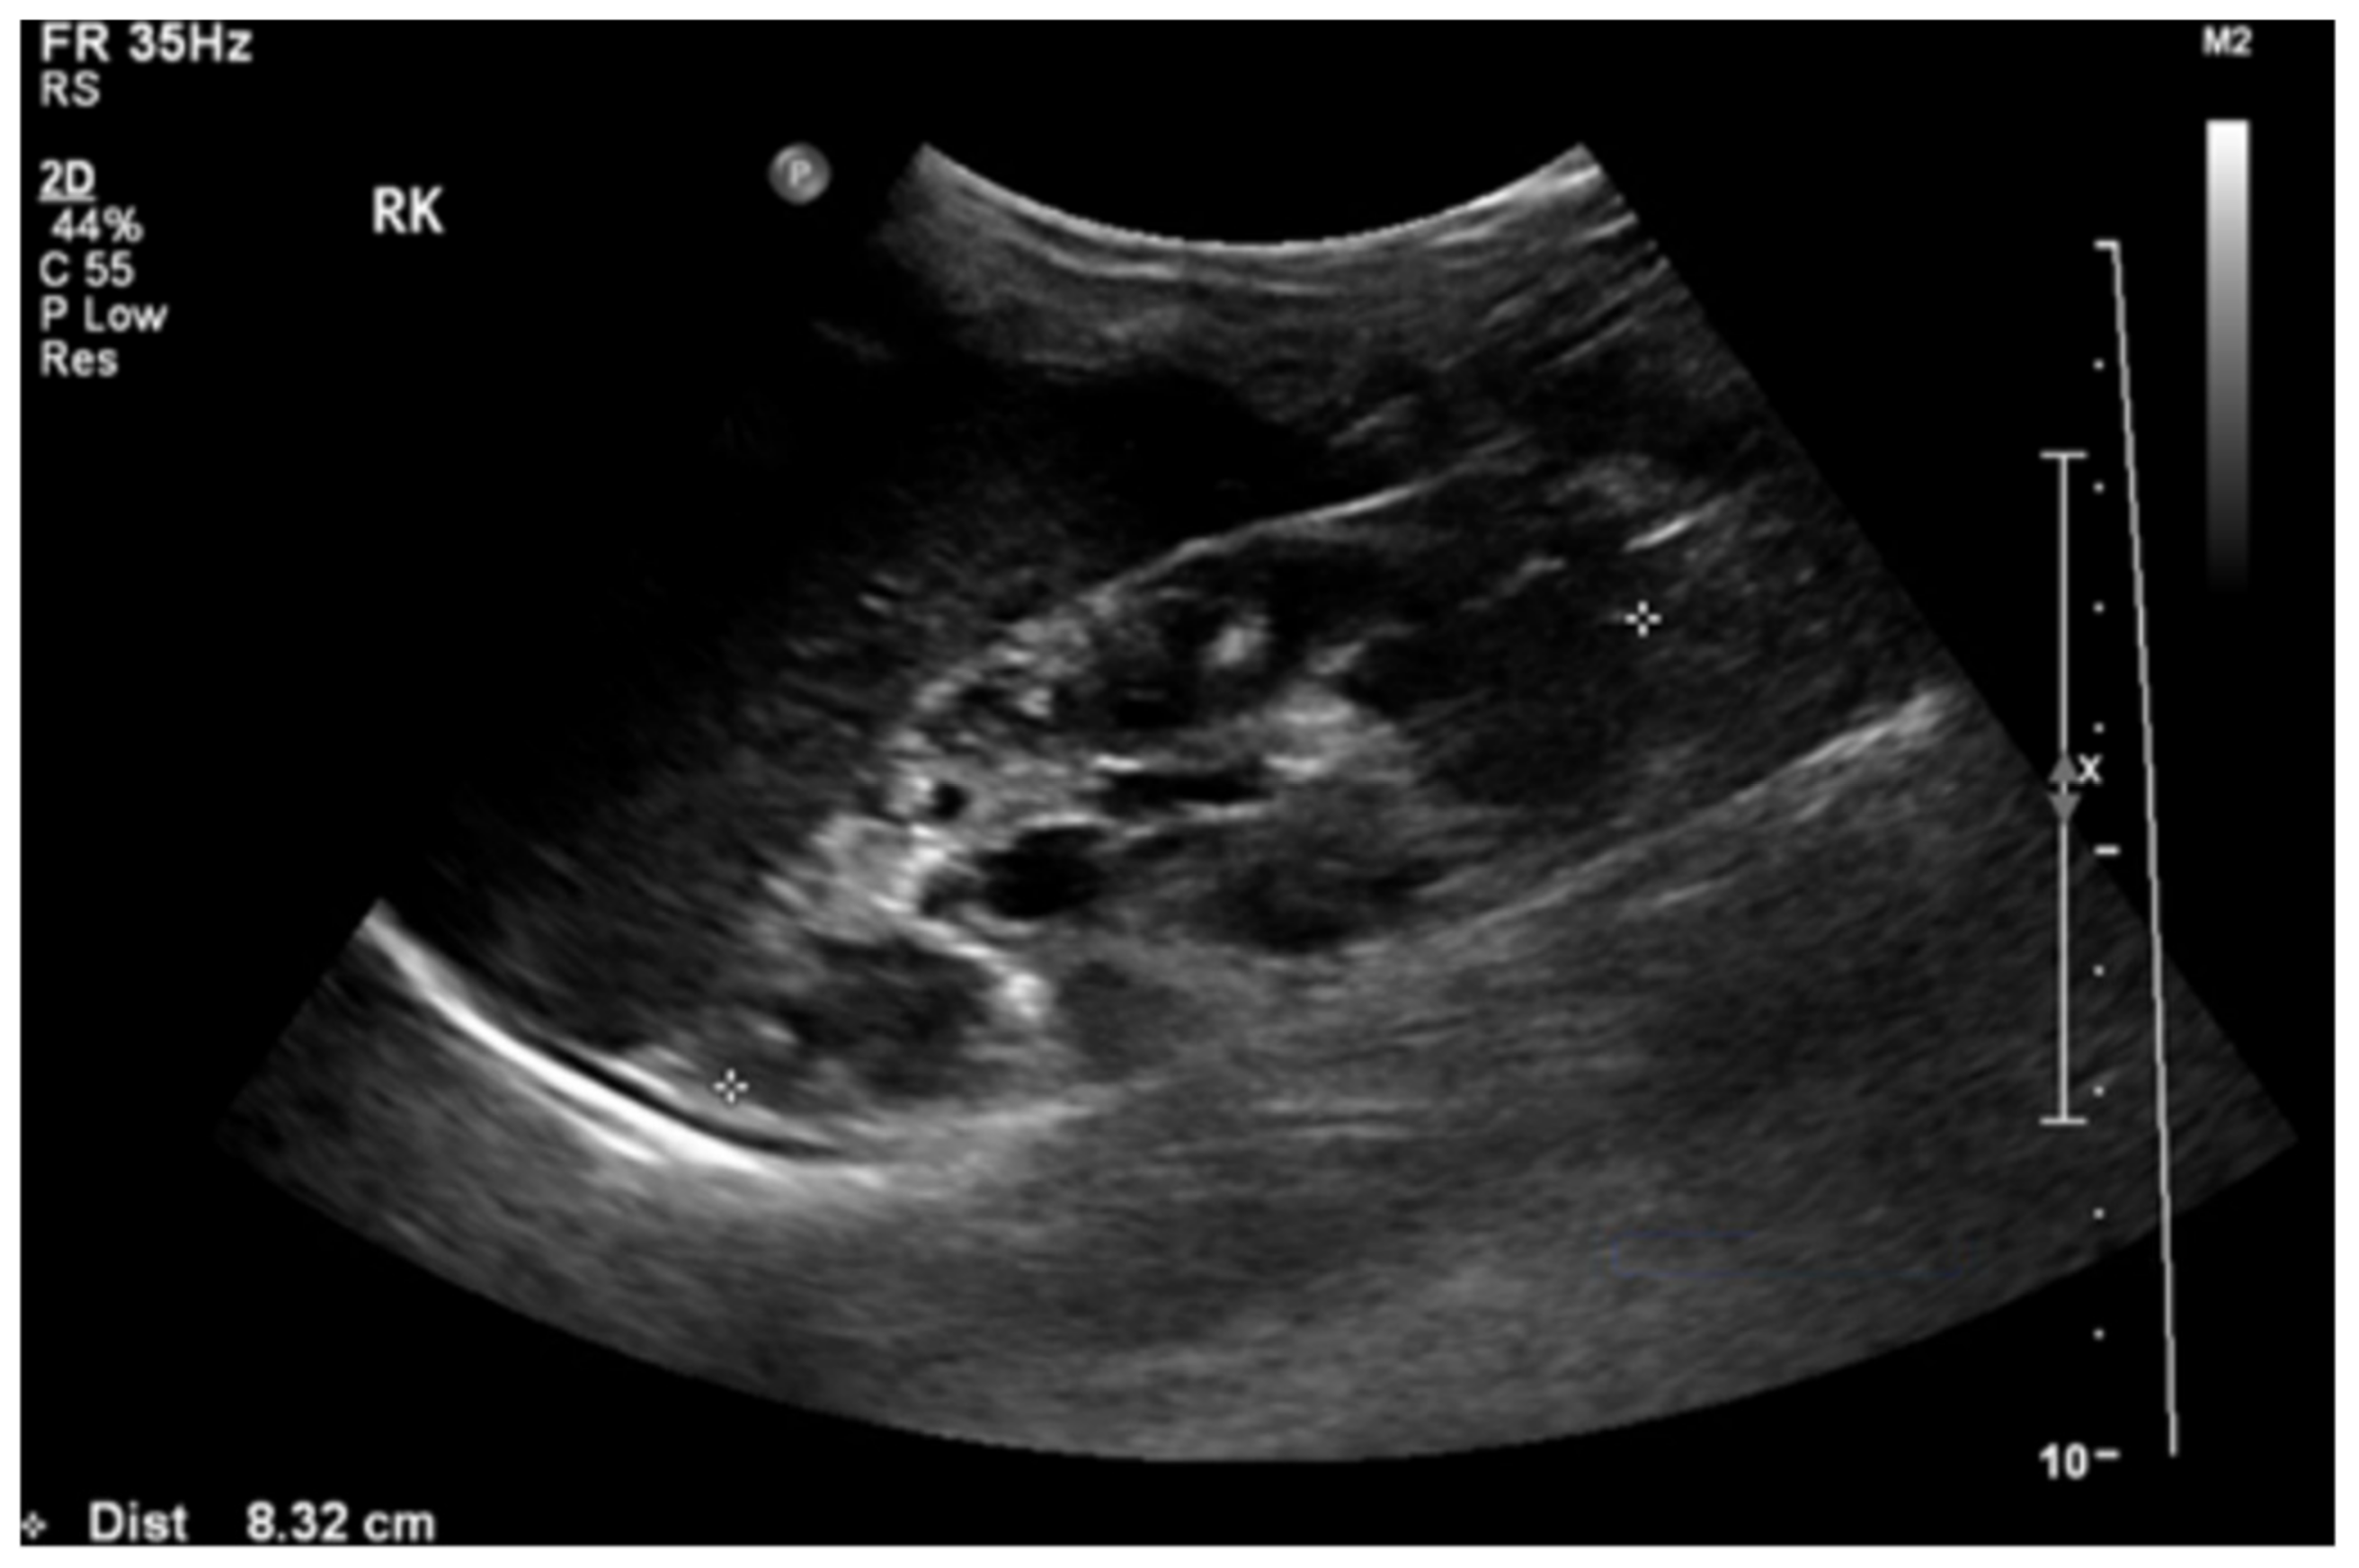

A doppler ultrasound revealed focal stenosis at the proximal and mid-portion of the left renal artery, with the raised peak systolic velocity reaching 300 cm/s. There were multiple cysts with no intra-cystic solid component in her right kidney (Figure 2). There were no cysts in the left kidney or liver. Tc99m-MAG3 (99m technetium mercaptoacetyltriglycine) scan showed impaired right renal function with a left-to-right ratio of 68%:32%.

Figure 2.

Renal ultrasound showed loss of corticomedullary differentiation of the right kidney with multiple cysts of variable sizes.